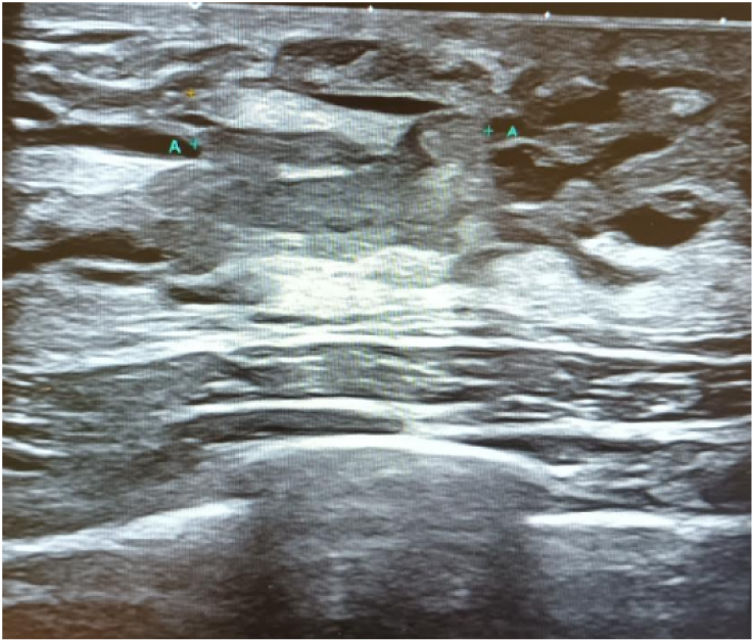

Inicialmente se solicitó la realización de una ecografía de la mama afecta, en la que se observó leve ectasia ductal en dicha mama, identificándose en la región retroareolar un nódulo intraductal de aproximadamente 1,7cm de extensión con doppler positivo, breast imaging reporting and data system4 (BI-RADS 4) (figs. 1 y 2). A continuación, se solicitó un estudio citológico de la muestra obtenida, que arrojó un resultado indeterminado. Posteriormente, se realizó una biopsia ecoguiada, y en el estudio anatomopatológico se observó un papiloma intraductal sin atipia.